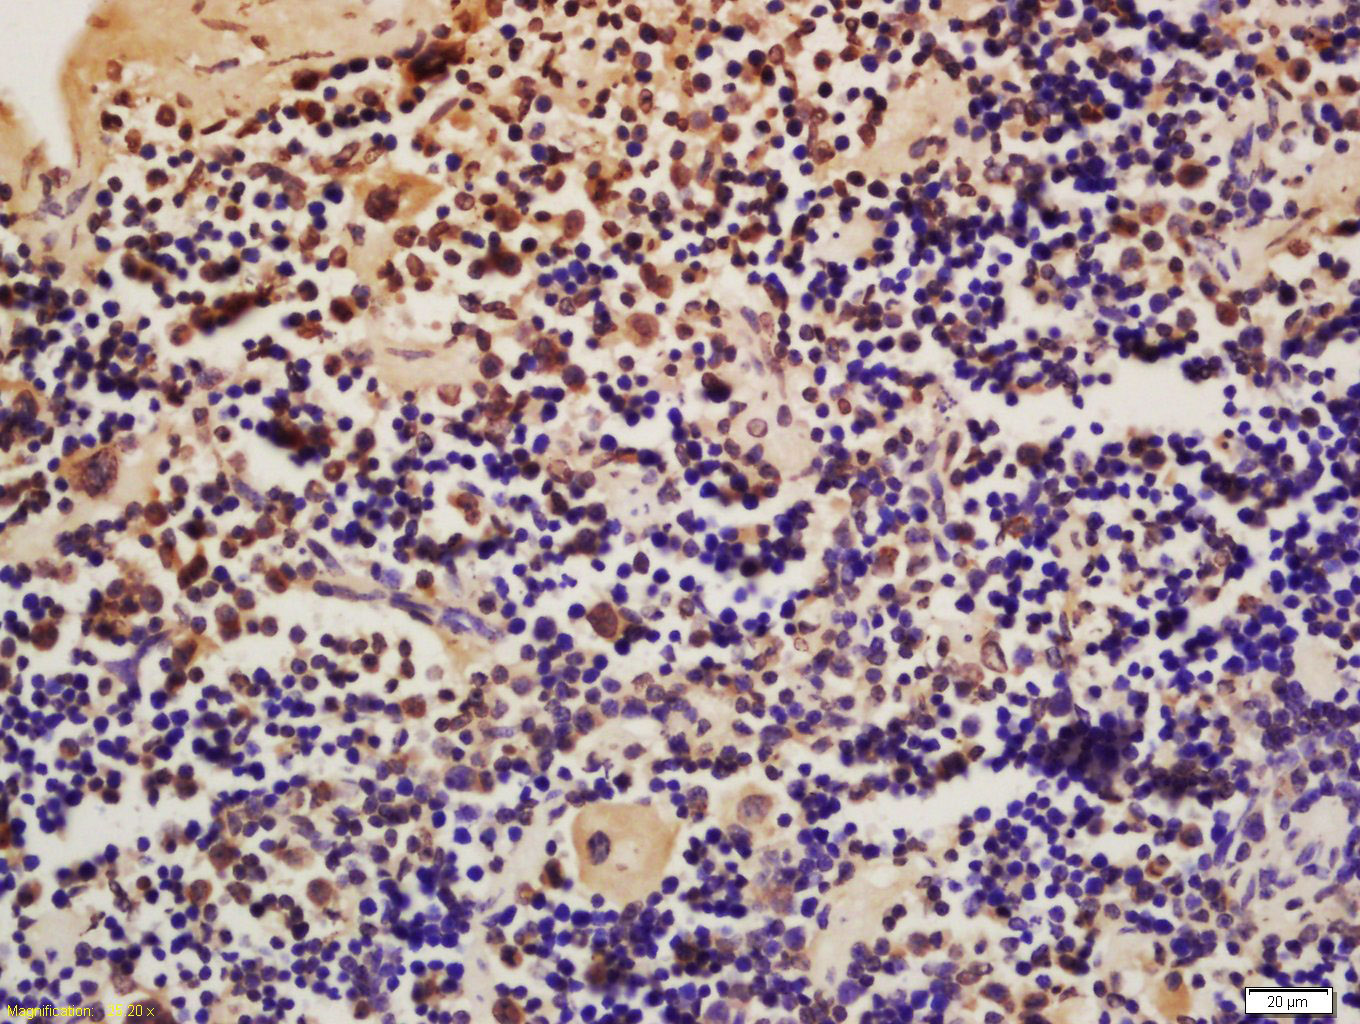

Tissue/cell: mouse spleen tissue; 4% Paraformaldehyde-fixed and paraffin-embedded; Antigen retrieval: citrate buffer ( 0.01M, pH 6.0 ), Boiling bathing for 15min; Block endogenous peroxidase by 3% Hydrogen peroxide for 30min; Blocking buffer (normal goat serum,C-0005) at 37℃ for 20 min; Incubation: Anti-Nucleoprotein TPR Polyclonal Antibody, Unconjugated(bs-5755R) 1:200, overnight at 4°C, followed by conjugation to the secondary antibody(SP-0023) and DAB(C-0010) staining